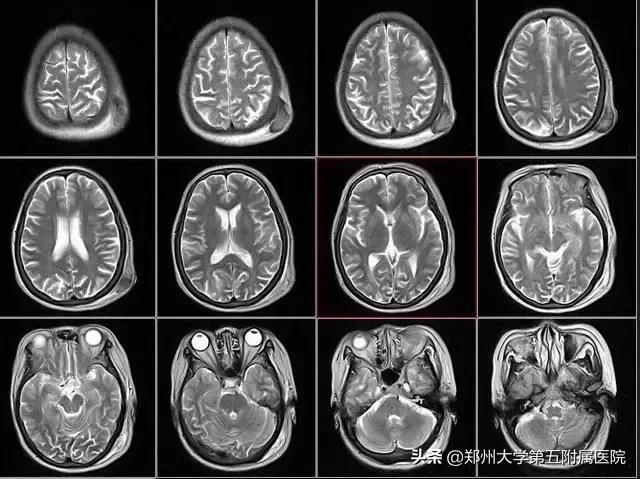

MRI对人体没有电离辐射损伤;MRI能获得原生三维断面成像而无需重建就可获得多方位的图像;软组织结构显示清晰,对中枢神经系统、膀胱、直肠、子宫、阴道、关节、肌肉等检查优于CT。尤其是关节、肌肉、中枢神经系统等软组织的检查结构更清晰。核磁共振对脊柱、关节、肿瘤、感染性疾病、淋巴结和血管结构之间的相互鉴别,有独到的优势。

1、脑和脊髓粗看CT,细看核磁共振。